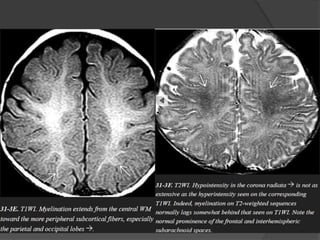

 Normal myelination… Hyperintense on T1 &

Hypointense on T2.

 T1W parallel increase in lipids while T2W

correlates to the period of maturation of myelin

sheath.